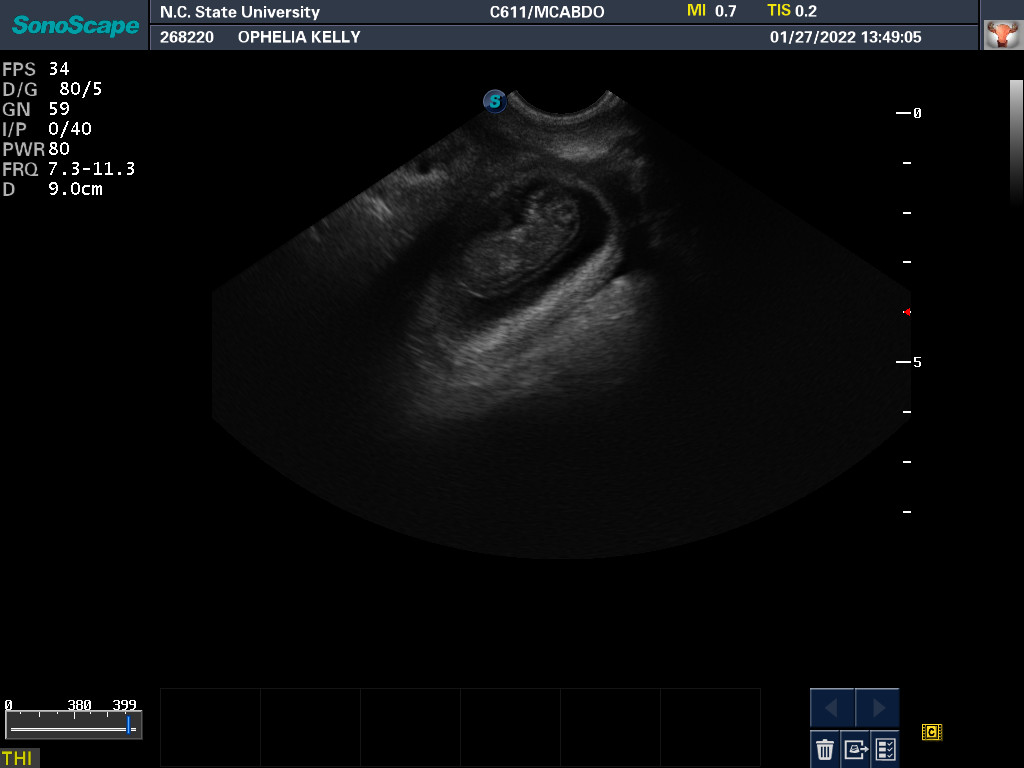

27 Jan 2022

Ultrasound today by the theriogenology (reproduction) veterinarians at NC State University showed that Ophelia is pregnant with three puppies, possibly four puppies. (It can be difficult to accurately count puppies using ultrasound.)

This morning Ophelia did not want to eat any breakfast. As I was going to Raleigh on other business, I took Ophelia to be checked out by my repro vets. After examining Ophelia, ultrasounding the puppies, and testing Ophelia's progesterone, the vet assured me that everything looked normal. When a dog has a lot of puppies, there is less room for a lot of food in the stomach. So it looks like going forward I will be feeding Ophelia lots of small meals.

The x-ray also revealed that it is unlikely that Ophelia will be able to free-whelp the puppies. The size of the skulls of the puppies is larger than Ophelia's pelvic opening. This is called fetal-pelvic misproportion (or more technically cephalopelvic disproportion), and in my opinion is the reason many Norwich have difficulty free-whelping. So we are planning on a c-section for Ophelia. From now until the c-section, every morning I will be taking Ophelia to NC State, where my repro vets will test her progesterone level and check the status of the puppies via ultrasound. When the puppies are sufficiently "cooked" (developed), they will do a c-section. Most likely this will be Thursday based upon when Ophelia ovulated.